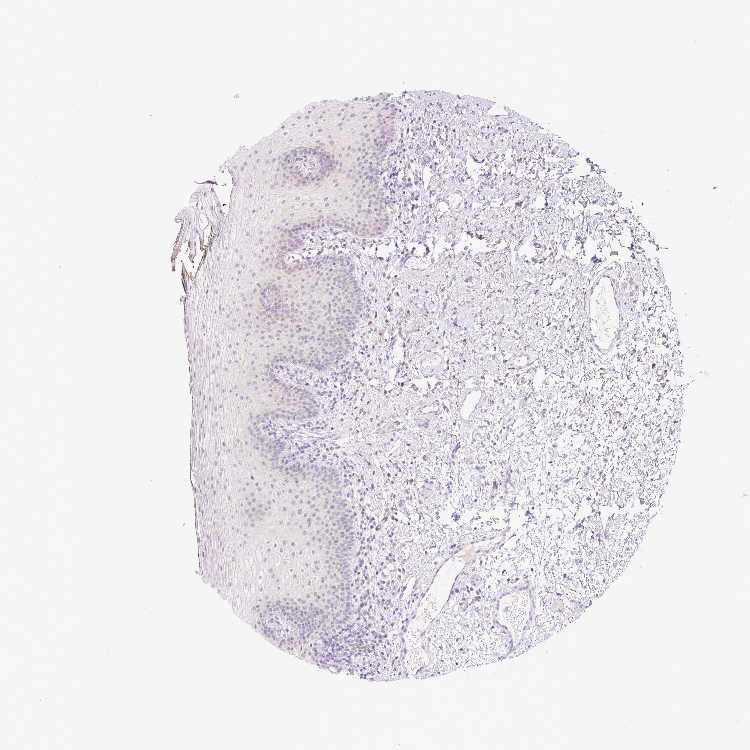

TISSUE PRIMARY DATA ORAL MUCOSA Show tissue menu

Oral mucosa

ORAL MUCOSA - Antibody stainingi

Antibody staining in the annotated cell types in the current human tissue is reported as not detected, low, medium, or high, based on conventional immunohistochemistry profiling in selected tissues. This score is based on the combination of the staining intensity and fraction of stained cells.

Each image is clickable and will lead to virtual microscopy that enables deeper exploration of all samples and also displays staining intensity scores, fraction scores and subcellular localization as well as patient and tissue information for each sample.

Antibody HPA046985Antibody HPA053526

Squamous epithelial cells Not detectedNot detected